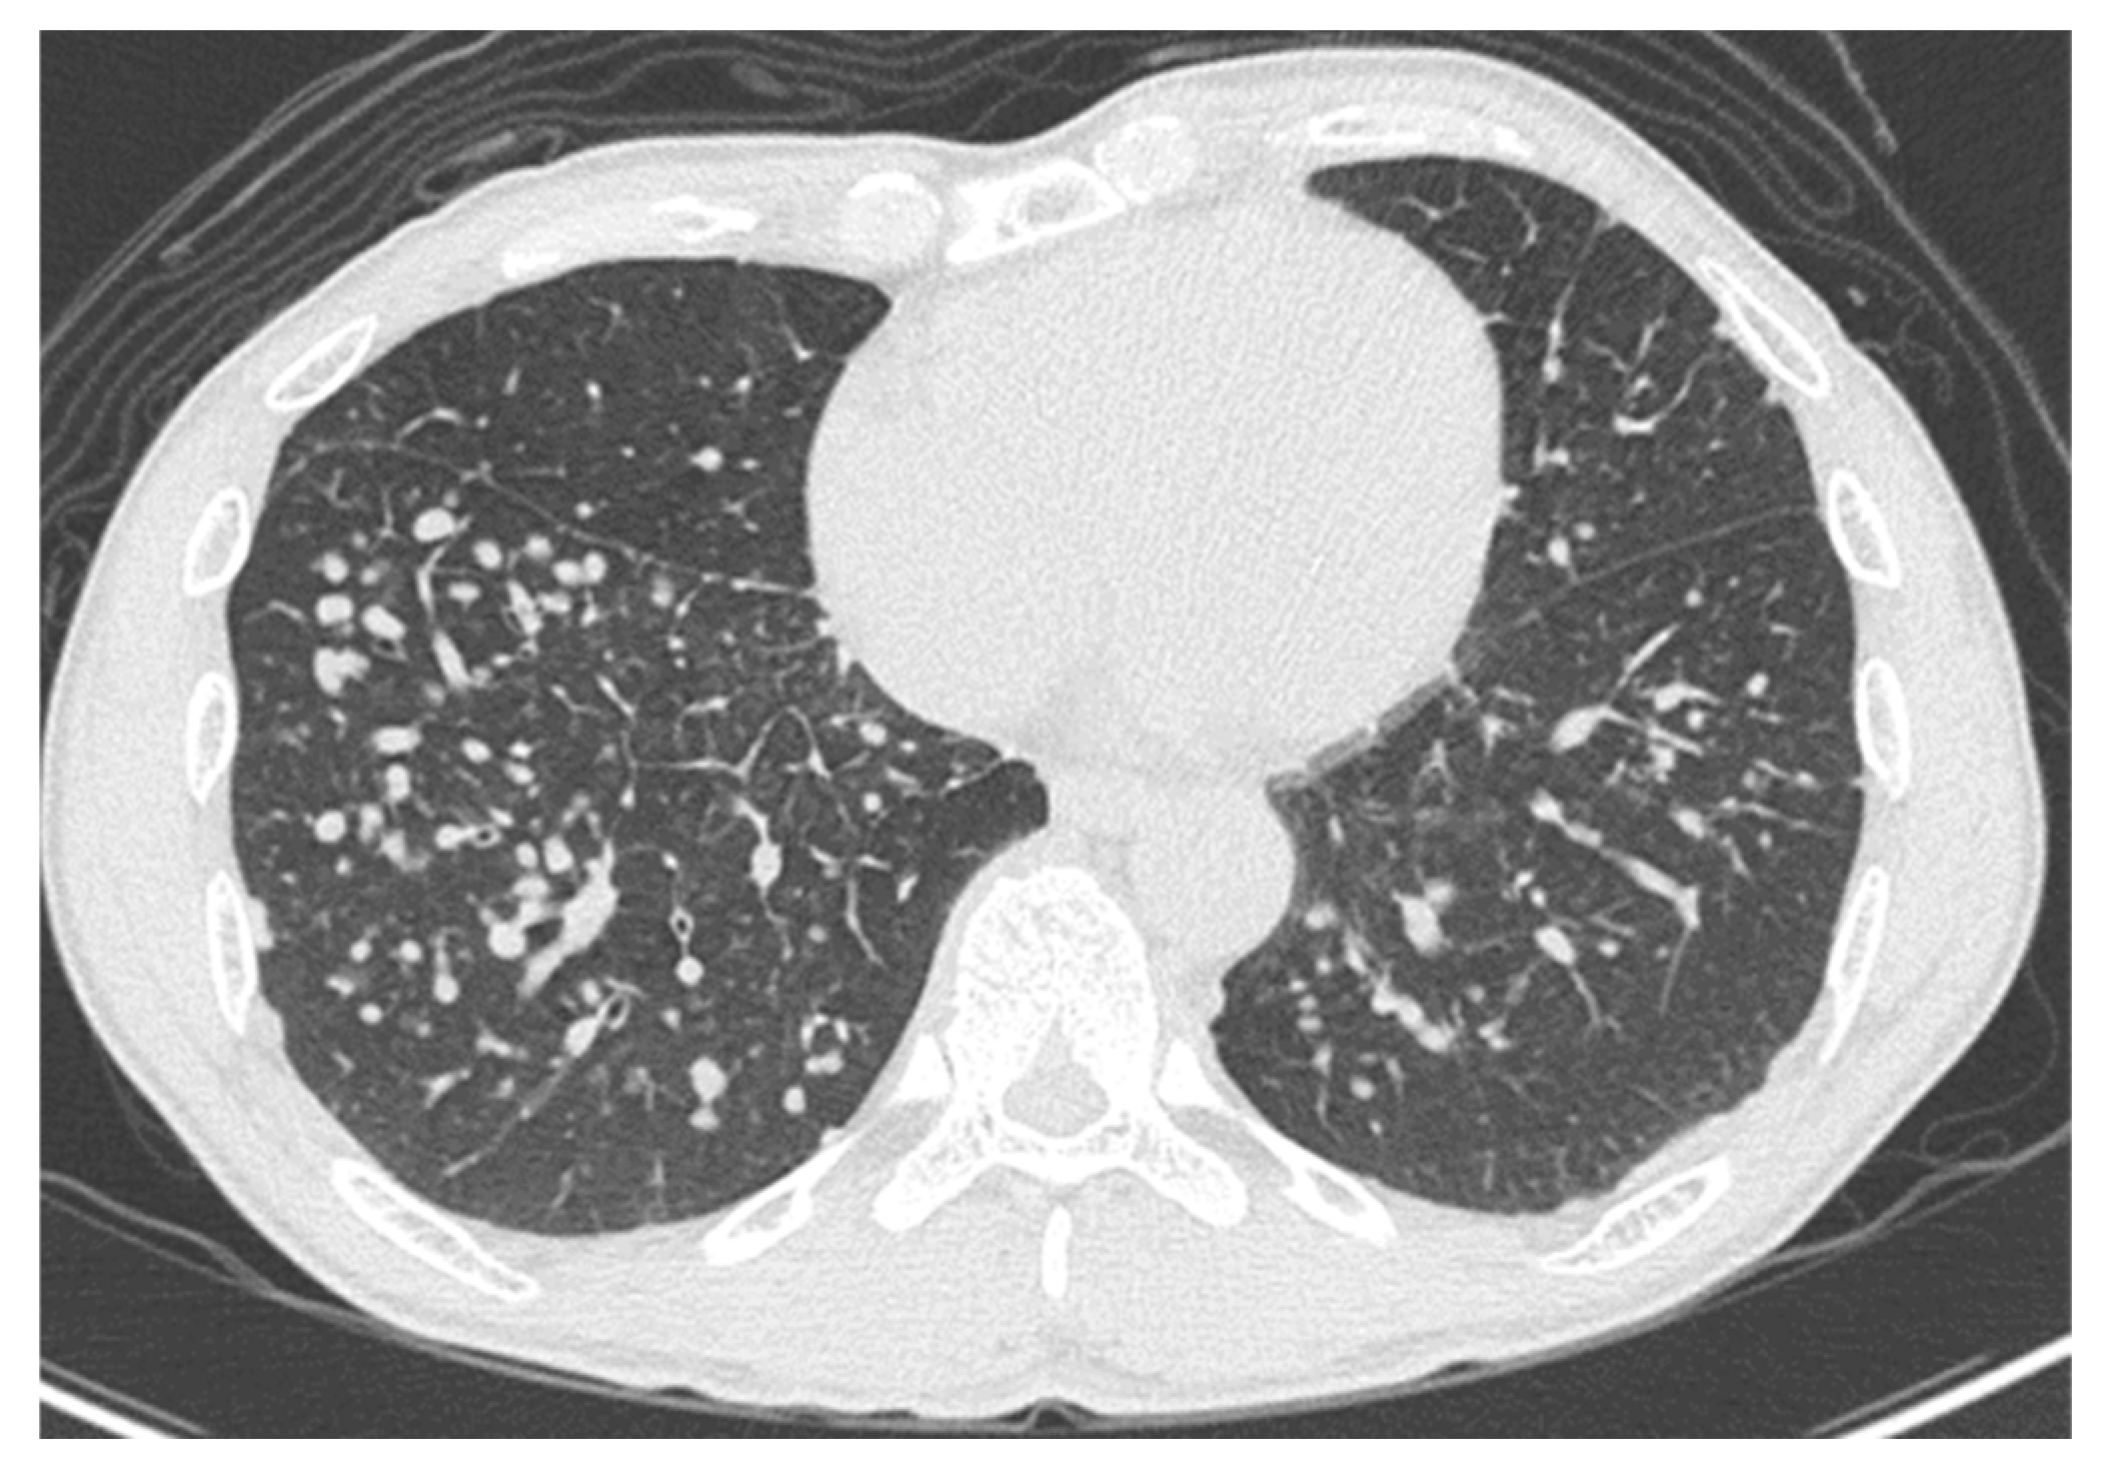

High-resolution computed tomography (HRCT) (Figure 2) showed well-defined multiple centrilobular and perilobular nodules, and thickening of the intralobular septa in the middle and lower zones of both lungs. No pleural effusion or mediastinal lymphadenopathy was observed.

Figure 2.

High-resolution computed tomography of the lower lung lobes on admission, showing well-defined multiple centrilobular and perilobular nodules, and thickening of the intralobular septa in the middle and lower zones of both lungs.